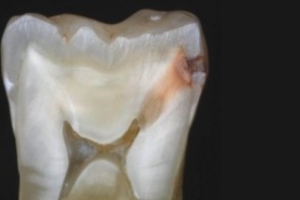

Zobu bojāejas gadījumā vai pēc zobu traumas, kad baktērijas sasniedz celulozes audus, rodas iekaisums – pulpīts. Ja zobārsts netiek laikus konsultēts, pulpas audi atmirst un infekcija izplatās uz apkārtējiem audiem. Pēc tam tiek bojāts kauls ap zoba sakni, attīstās abscess – apikālais periodontīts – un, audiem turpinot bojāties, veidojas cista.

Ja sakņu kanāli netiek ārstēti, baktērijas caur zoba saknes augšējo daļu iekļūst apkārtējos audos, izraisot periodonta audu iekaisumu un kaula bojāeju. Tas var izraisīt zobu sāpes sakodiena laikā un sejas mīksto audu pietūkumu. Tas var izraisīt arī abscesu smaganās – fistulu -, kas ved uz cēloņa zoba saknes virsotni. Šādā gadījumā zobu sāpes var nebūt. Endodontisko ārstēšanu izmanto, ja zobu sakņu kanālā esošos mīkstos audus – celulpu (kurā atrodas asinsvadi un nervi) – ir bojājusi infekcija un tā ir iekaisusi. Visbiežākais iemesls ir neārstēts zobu kariess, kas ir ne tikai bojājis emalju un dentīnu, bet arī sasniedzis zoba pulpu. Tas var izraisīt stipras zobu sāpes, kas var rasties spontāni vai pastiprināties temperatūras ietekmē. Bieži vien intensīvas sāpes sākas vēlu vakarā vai naktī un var izplatīties uz apkārtējām zonām, piemēram, ausu un degunu. Pacientam var būt grūti noteikt, kurš zobs sāp. Pretsāpju līdzekļi sāpes var nemazināt.